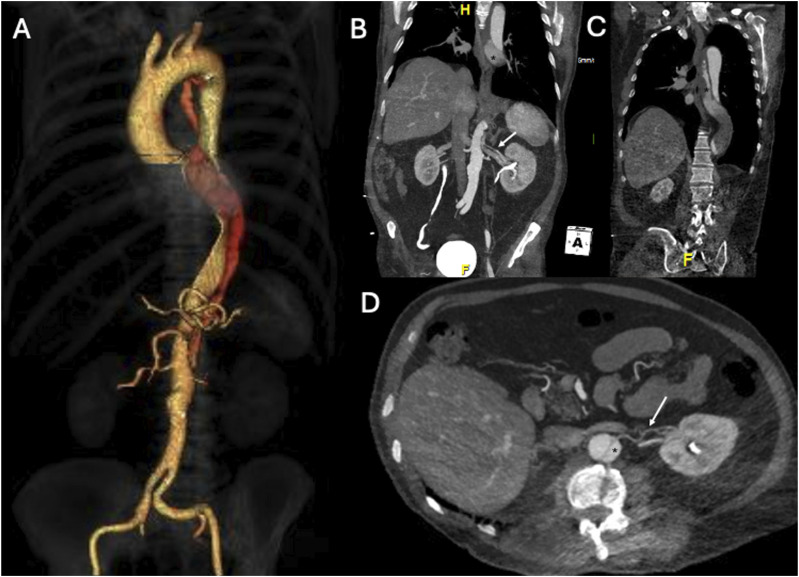

目的:描述在一名接受保守治疗的慢性 B 型主动脉夹层(cTBAD)患者中,采用偏离中心的球囊扩张覆盖支架选择性封堵远端入口撕裂(ET)的技术:一名 63 岁的男性,因慢性 B 型主动脉夹层(cTBAD)接受保守治疗,在随访时出现 FL 部分血栓形成和扩张(胸主动脉 FL 在 6 个月内从 21 mm 增至 27 mm,腹主动脉 FL 在 6 个月内从 11 mm 增至 15 mm)。未发现近端 ET。FL远端灌注是由腹主动脉中的ET造成的,ET为2毫米的肾脏附属动脉(ARA)供血。由于主动脉直径低于血管内修复的阈值,因此计划对远端 ET 和 ARA 进行选择性闭塞。对球囊扩张覆盖支架进行了改良,将覆盖支架向近端偏离中心,使其在穿过 ET 进入 ARA 后形成漏斗状闭塞。为防止术中检测到的膈动脉(PA)可能导致的FL扩张造成Ic型内漏,在改良支架和ARA的管腔内部署了线圈。出院前的计算机断层扫描血管造影显示,ARA和ET均被排除,PA出现了2型内漏:结论:球囊扩张型覆膜支架可通过偏离覆膜支架的中心形成漏斗状来进行改造,以适应不同直径的要求。

PurposeTo describe the technique of off-centering a balloon-expandable covered stent for selective occlusion of a distal entry tear (ET) in a patient, conservatively treated for chronic type B aortic dissection (cTBAD), presenting FL expansion.TechniqueA 63-year-old male, with conservatively managed cTBAD, presented at follow-up with FL partial thrombosis and expansion (thoracic aorta FL from 21 mm to 27 mm and abdominal aorta FL from 11 mm to 15 mm in 6 months). No proximal ET was identifiable. Distal FL perfusion was caused by an ET in the abdominal aorta feeding a 2 mm accessory renal artery (ARA). As the aortic diameter was below the threshold for endovascular repair, a selective occlusion of the distal ET and ARA was planned. A balloon-expandable covered stent was modified by off-centering the covered stent proximally and resulting in a funnel-shape occluder after deployment across the ET into the ARA. To prevent type Ic endoleak due to possible FL expansion caused by an intra-operatively detected phrenic artery (PA), coils were deployed into the lumen of the modified stent and the ARA. The pre-discharge computed tomography angiography showed exclusion of both the ARA and ET and a type 2 endoleak from the PA.ConclusionA balloon-expandable covered stent can be modified by off-centering the covered stent resulting in a funnel shape to adapt to different diameter requirements.